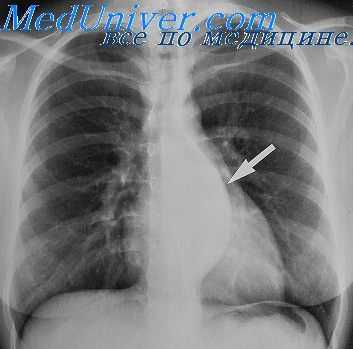

Обзорная рентгенография грудной клетки может лишь ориентировочно указывать на мезотелиому плевры такими признаками, как наличие массивного гидроторакса, утолщение париетальной плевры, уменьшение объема грудной полости, смещение органов средостения. УЗИ плевральной полости позволяет определить объем экссудата в плевральной полости, а после его эвакуации оценить состояние серозной оболочки легкого.

Рентгенография в прямой проекции при невриноме средостения